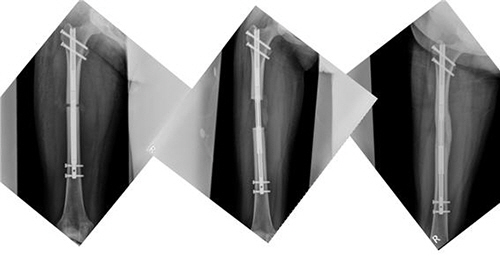

하지부동이란 양쪽 다리 길이가 다른 증상이다. 사람의 몸이 완벽한 대칭은 아니지만 사고나 어린 시절의 골절 등으로 보행에 불편함을 느낄 만큼 차이가 나면 수술 대상이 된다. 기존의 하지부동은 외고정장치를 이용한 연장만 가능했는데, 지난 9월 내고정장치인 프리사이스가 신의료기술을 통과하면서 이젠 하지부동 환자들에게도 프리사이스 사용이 가능해졌고 이미 본격적인 수술이 시행되고 있다. 아시아 최초/최다 프리사이스 수술 집도, 국내 프리사이스 하지부동 수술 1호 집도의. 언제나 타이틀이 따라다니는 전 세브란스 정형외과 교수인 이동훈 박사의 이동훈연세정형외과에는 요즘 하지부동 환자들의 내원이 부쩍 늘었다.

이동훈연세정형외과의 이동훈 박사는 "키 크는 수술에 이어 하지부동 환자들에게도 프리사이스 수술을 하게 되면서 정말 좋은 결과를 경험하고 있다. 의사로서도 기쁜 일이지만 더 행복해하는 환자들의 모습을 보며 보람을 느낀다." 라고 소감을 전했다.